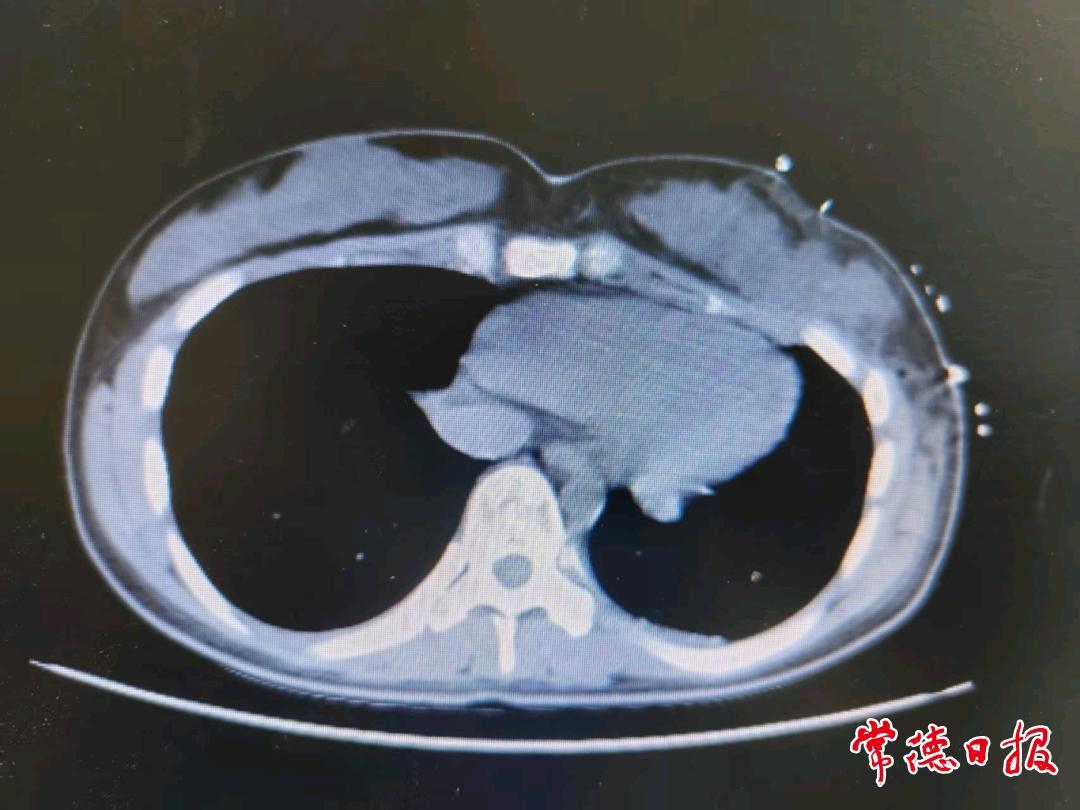

意识到问题的严重性后,家长立即带小美就医检查,彩超结果令人震惊:左侧乳房内竟长着一个巨大的肿瘤。随后,小美来到常德市第二人民医院寻求治疗,经详细检查和穿刺活检,最终确诊为幼年性乳腺纤维瘤,属于良性病变。尽管是良性,但其体积巨大(术前影像显示如柚子大小),必须尽快手术切除。经过周密的术前准备,医师团队为小美成功实施了肿瘤切除手术。手术过程顺利,术后小美恢复良好。